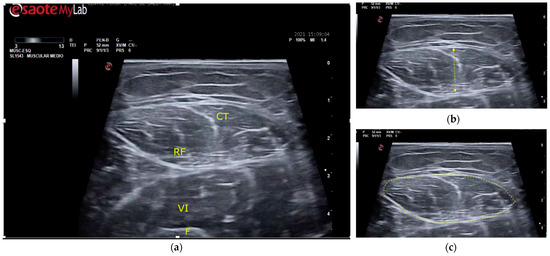

Figure 1.

Ultrasound of the rectus femoris muscle for MT and CSA measurement points. (a) Guiding structures are shown for proper recognition. RF, rectus femoris muscle; CT, central tendon of RF; VI, vastus intermedius muscle; F, femur. (b) MT (muscle thickness) was determined as the distance between the superior and inferior aponeurosis of the RF. (c) CSA (cross-sectional area) was measured by delimiting the cross-sectional area of the RF.

The MT and CSA of the rectus femoris of the dominant or uninjured leg were measured using B-mode on the MyLab™ Seven (Esaote, Genoa, Italy) (Figure 1). All measurements were done at maximal muscle bulk and performed by the same experienced investigator, following the SARCUS protocol for evidence-based muscle assessment though ultrasound [20,21]. The measurement protocol is described in Table 1. Anatomic landmarks and measuring points are shown in Figure 2. All measures were conducted at admission to the post-acute care unit (baseline) and every seven days until discharge, up to a 2-week follow-up.